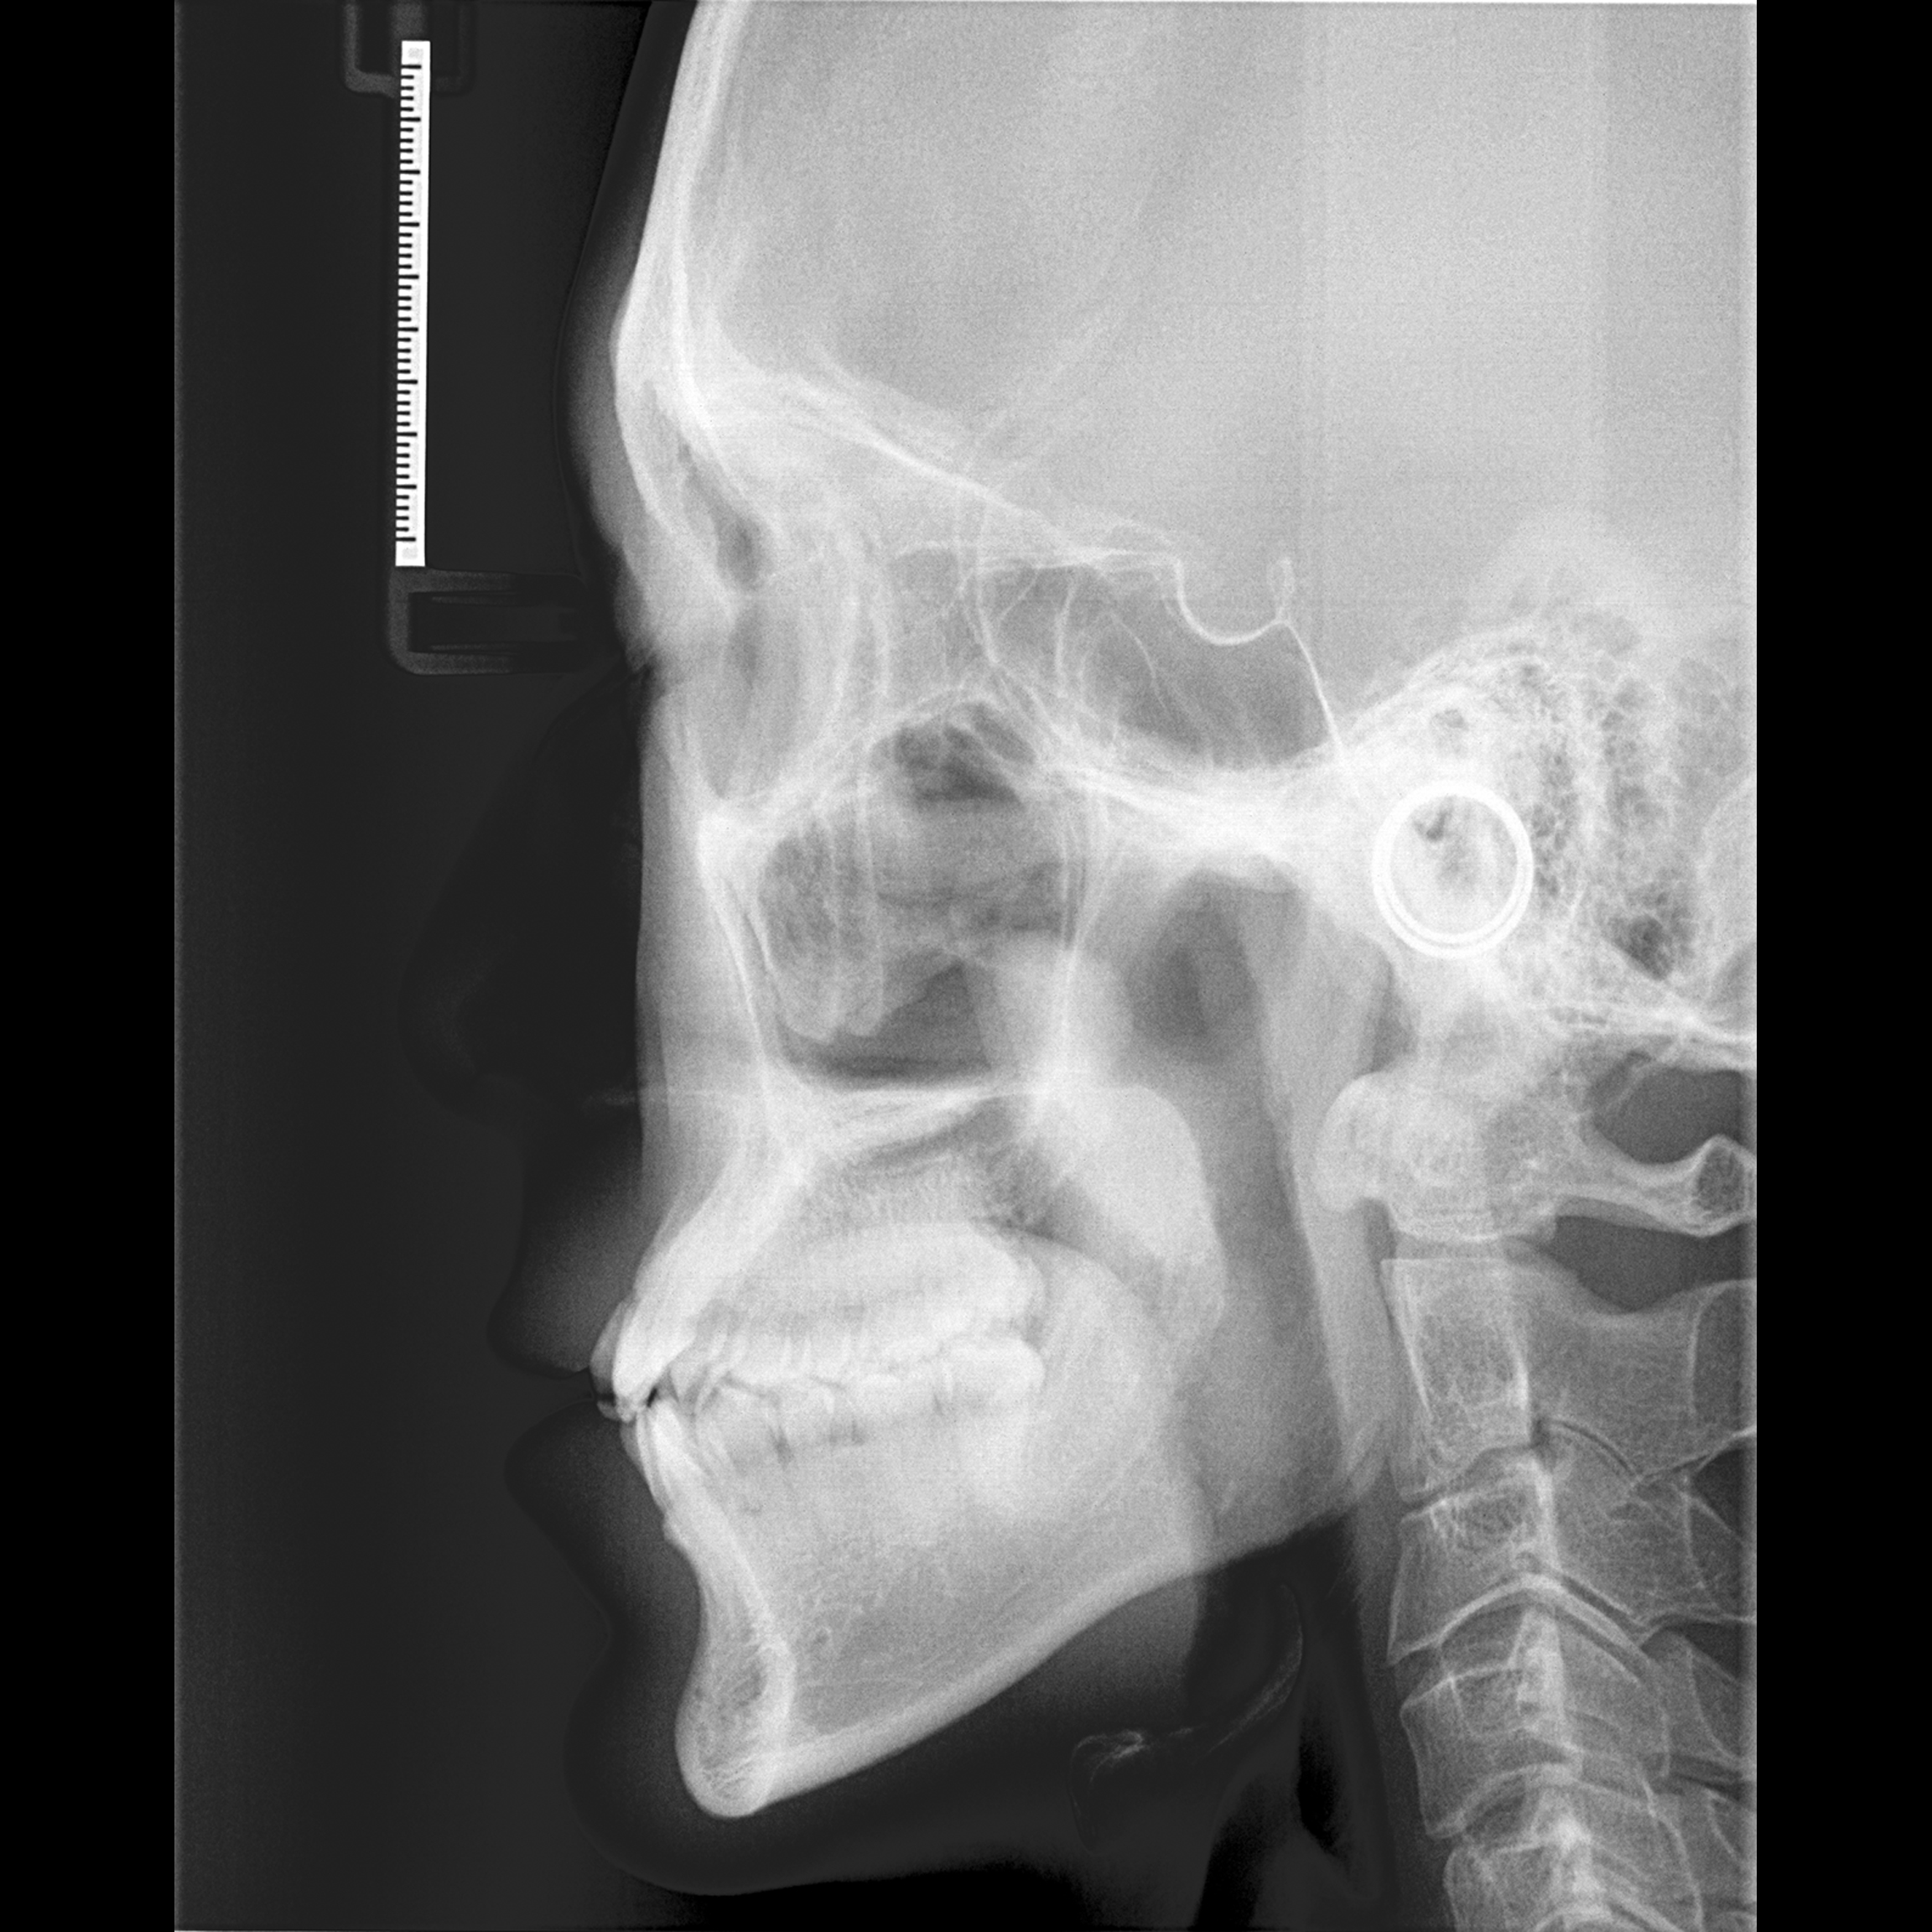

Lateral cephalogram and orthopantomogram (OPG) radiographs are routinely taken for each orthodontic patient for diagnostic and treatment planning purpose. Compared with panoramic radiograph, lateral cephalogram contains the entire craniofacial bones and soft tissue. Because of the way the lateral cephalogram were taken, the left and right craniofacial bones and teeth overlapped together, so the lateral cephalogram can provide more information than panoramic radiograph. However, no one has done any research to infer age and gender based on deep learning of lateral cephalogram.

Because the lateral cephalogram contains the cervical spine, all teeth and craniofacial bones, as well as the craniofacial soft tissue. Therefore, it can simultaneously reflect the aging changes of these areas. So far, the study of age estimation using lateral radiographs is still a blank, so we choose lateral radiographs as the research object.